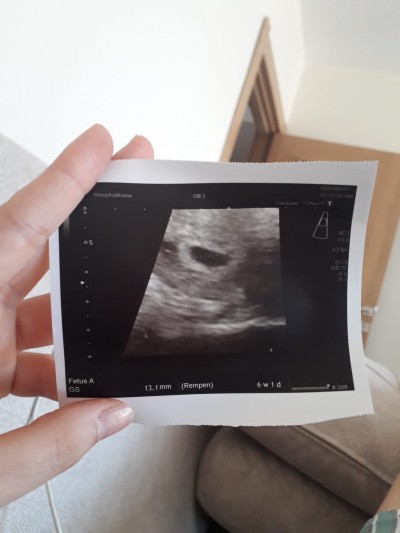

Kızlar 3 gün önce kanama oldu biraz açık özel bir doktora gittim ultrason da keseyi gördük 5+1 de iğne verdi bugün devlette gittim oda kese gayet güzel görünüyor biraz aşağıda dedi 3 gün önceki ultrason görüntüsü ile karşılaştırdık kese se büyüme göremiyorum ama 2 hafta daha bekleyelim dedim anlatan varsa bakabilir ki iki ultrason gorusuntusune

Gebelik haftası 6+1